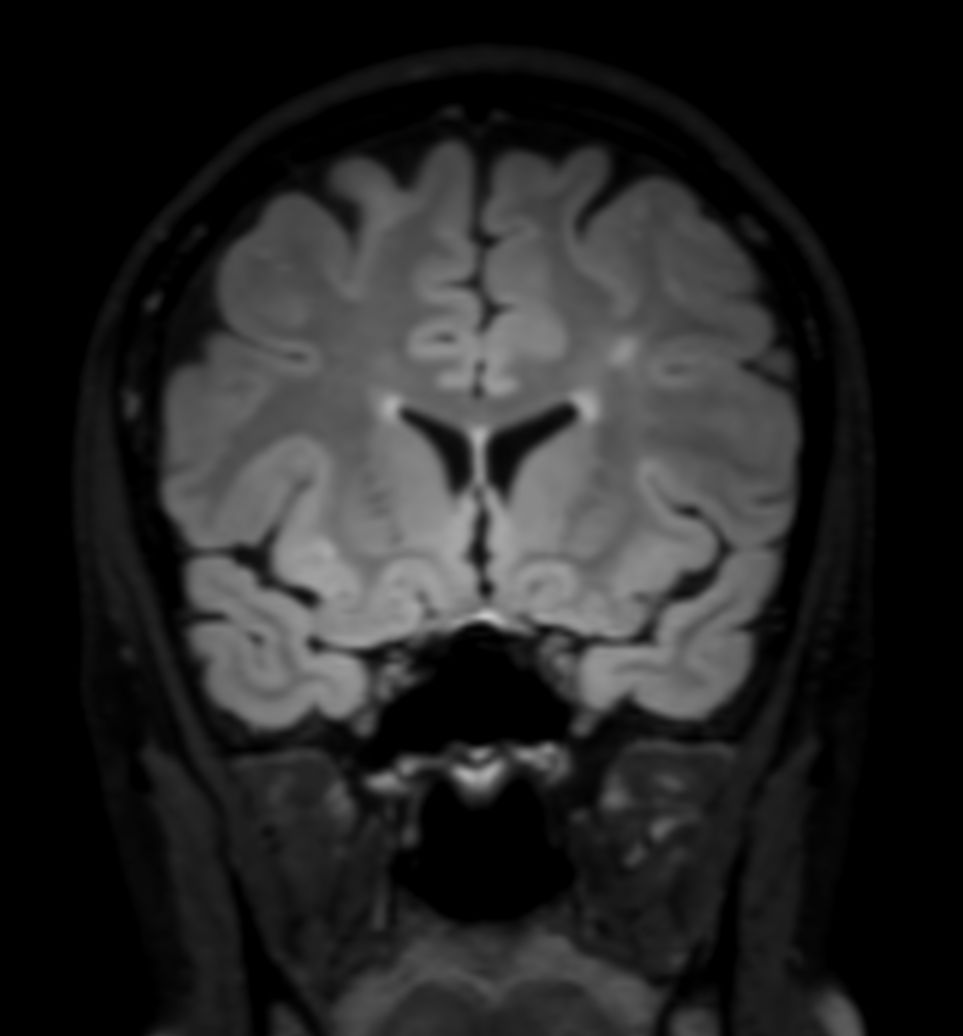

SWI sequence has a high sensitivity to enhance contrast for deoxygenated (venous) blood or calcium deposits. This may help, when used in combination with other clinical information, in the diagnosis of various neurological pathologies. 3D imaging lets you acquire high resolution data in multiple directions in one scan. Isotropic voxel size enables reformats in any plane without loss of resolution. FLAIR* requires offline post processing combining the contrast of 3D FLAIR and 3D SWI EPI into a single image. This enables the visualization of Central Vein Sign, mapping subcortical veins onto 3D FLAIR contrast images.